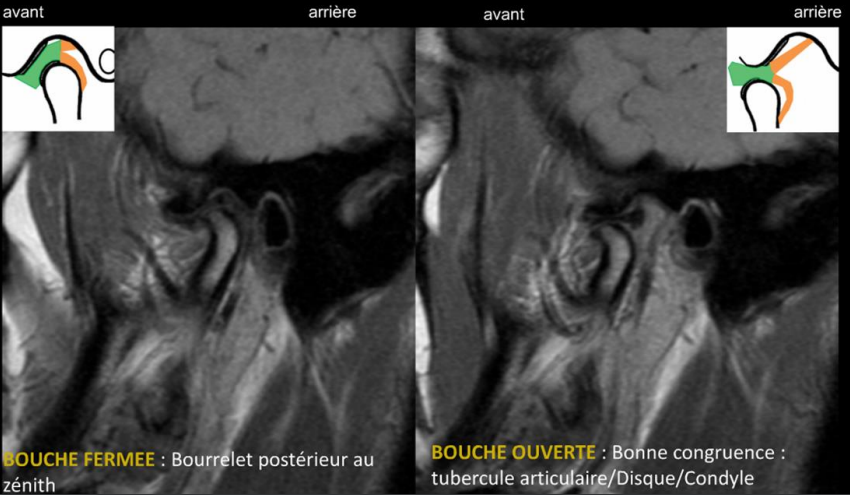

- Bouche fermée :

- bourrelet (attache ou bande) postérieur située à l'aplomb (+/- 10°) du centre du condyle ;

- Bouche ouverte :

- bonne congruence avec interposition de la partie intermédiaire du disque entre le condyle et l'éminence articulaire temporale.